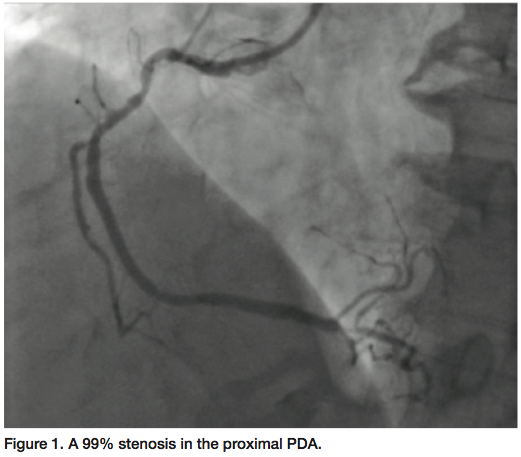

The diagnostic 5 French sheath was upsized to a 6 French Glidesheath (Terumo). A Hockey stick guide catheter was utilized to engage the right coronary system. Bivalirudin (Angiomax, The Medicines Company) was our choice of antiplatelet therapy. We initially performed FFR (Volcano Corporation) for the proximal portion of the RCA and the FFR was negative; therefore, at this point, the initial plan was to just stent the distal lesion. However, in an attempt to deliver a 2.5 x 12 mm Promus drug-eluting stent (Boston Scientific) into the

distal lesion, the guide backed out, and could not get though the calcification of the proximal portion. We elected to use IVUS to see the calcium (Figure 2). There were some difficulties passing the IVUS catheter. Minimum lumen diameter (MLD) was 3.19 with a percent diameter stenosis of 60% by IVUS, based on the reference vessel. Given the calcific nature of the disease and the IVUS finding, we elected to go ahead and proceed with revascularization of the